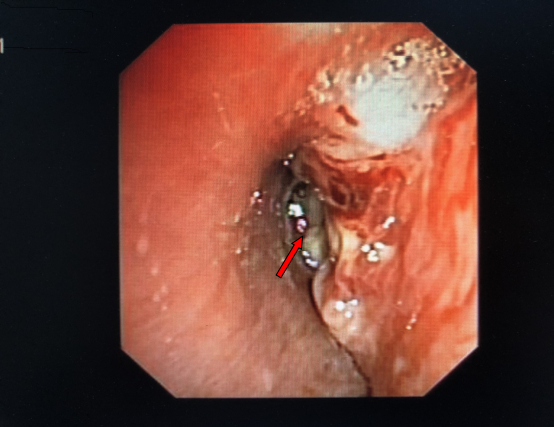

气管镜(术前):右主支气管及中间支气管新生物,堵塞大部分管腔

气管镜(术后):右主支气管及中间支气管管腔内大部分肿瘤组织被清除